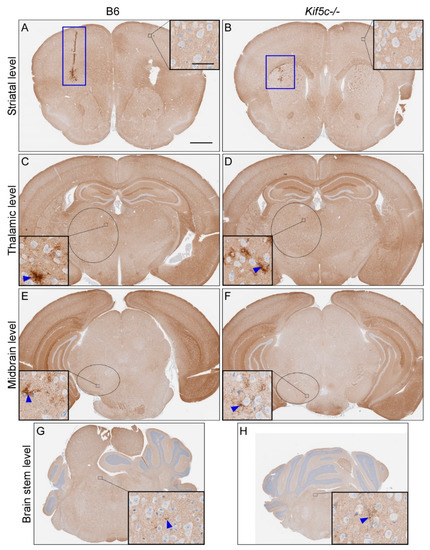

3.1. The 22 L PrPSc Spreading Kinetics in B6 and Kif5c−/− Mice

3.3. 22 L Scrapie-Infected Kif5c−/− and B6 Mouse Survival Curve and Neuropathology

| Scrapie Strain | Mouse Strain | Time Point (dpi 2) | Brain Region | |||||||||

|---|---|---|---|---|---|---|---|---|---|---|---|---|

| Striatum (0) 1 | Thalamus (3.2) 1 | Midbrain (5) 1 | Rostral Pons (7) 1 | |||||||||

| PrPSc Present 3 | PrPSc Score 4 | PrPSc Present 3 | PrPSc Score 4 | PrPSc Present 3 | PrPSc Score 4 | p-Value 5 | PrPSc Present 3 | PrPSc Score 4 | p-Value 5 | |||

| 22 L | B6 | 7 | 2/2 | 1 | 0/2 | 0 | 0/2 | 0 | 0/2 | 0 | ||

| Kif5c−/− | 7 | 2/2 | 1 | 0/2 | 0 | 0/2 | 0 | 0/2 | 0 | |||

| B6 | 25 | 5/5 | 2 | 5/5 | 1 | 3/5 | 0–1 | 0.46 | 4/5 | 0–1 | >0.99 | |

| Kif5c−/− | 25 | 3/3 | 2 | 3/3 | 1 | 3/3 | 1 | 2/3 | 0–1 | |||

| B6 | 40 | 4/4 | 3 | 4/4 | 2 | 4/4 | 2 | 4/4 | 1 | >0.99 | ||

| Kif5c−/− | 40 | 4/4 | 3 | 4/4 | 2 | 4/4 | 2 | 3/4 | 1 | |||

| B6 | 60 | 3/3 | 2–3 | 3/3 | 3 | 3/3 | 1–2 | 3/3 | 1–2 | |||

| Kif5c−/− | 60 | 3/3 | 3 | 3/3 | 3 | 3/3 | 2 | 3/3 | 1–2 | |||